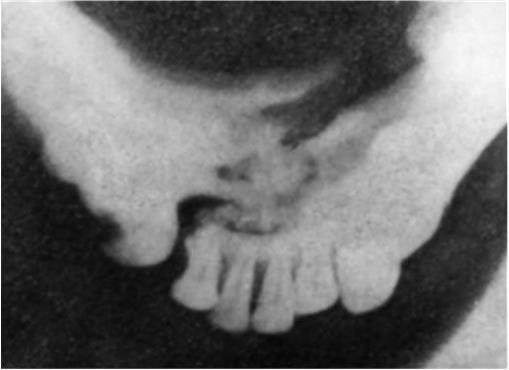

Используют также панорамную рентгенографию и, особенно, ортопантомографию нижней челюсти. Преимущество этого метода – возможность быстро получить ценную диагностическую информацию о состоянии зубов и нижней челюсти (при панорамной рентгенографии – особенно в переднем отделе челюсти).

Ортопантомографическое исследование позволяет на одном снимке проследить за изменениями, возникшими в результате перелома нижней челюсти на всем ее протяжении (рис. 5).

Рис. 3. Отпечаток с рентгенограммы подбородочного отдела нижней челюсти «на прикус». Отчетливо определяется перелом тела челюсти на уровне передних зубов